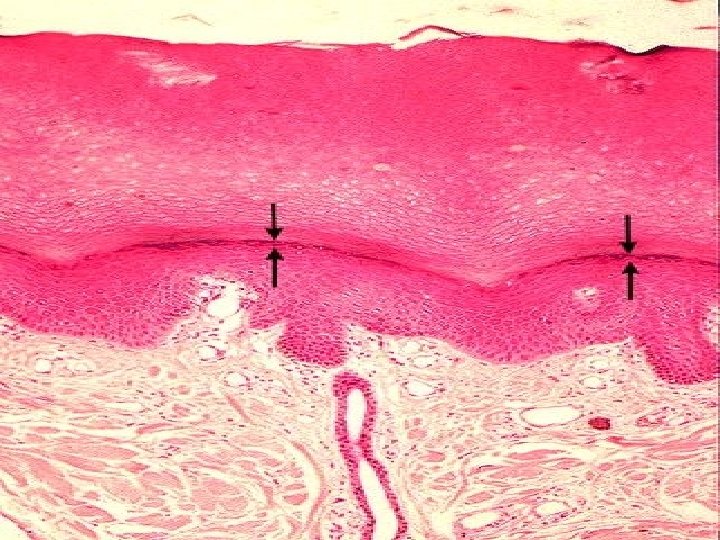

TYPES OF SKIN • Thin skin – covers all parts of the body except for the palms and palmar surfaces of the digits and toes. – lacks epidermal ridges – has a sparser distribution of sensory receptors than thick skin. • Thick skin (0. 6 to 4. 5 mm) – covers the palms, palmar surfaces of the digits, and soles – features a stratum lucidum and thick epidermal ridges – lacks hair follicles, arrector pili muscles, and sebaceous glands, and has more sweat glands than thin skin.

Specific Layer of the Epidermis Stratum Lucidum: • Observed only in nonhairy or thick skin. Several layers of dead cells with indistinct boundaries Stratum Corneum: • Composed of 25 or more layers of dead squamous cells still joined by desmosomes. Eventually desmosomes break and cells flake off in a process called desquamation